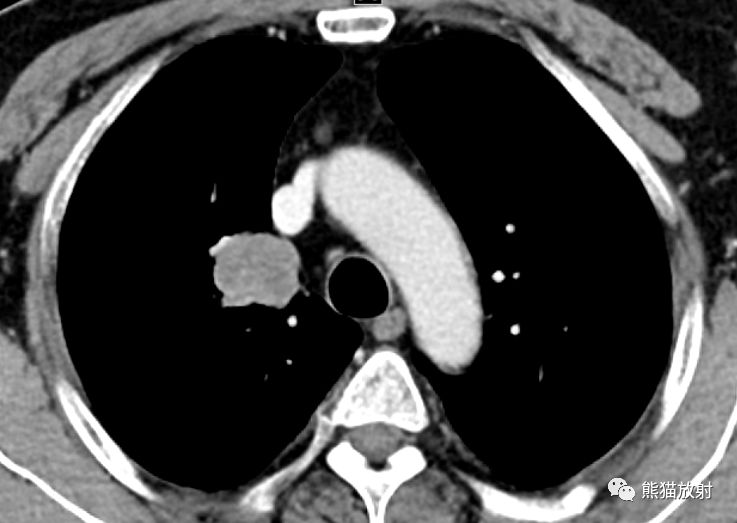

男,57岁,右肺上叶肺鳞癌(实性、有分叶、中度强化),右肺中叶黏液腺癌(病灶近胸膜,形态不规则,术前诊断有难度)。